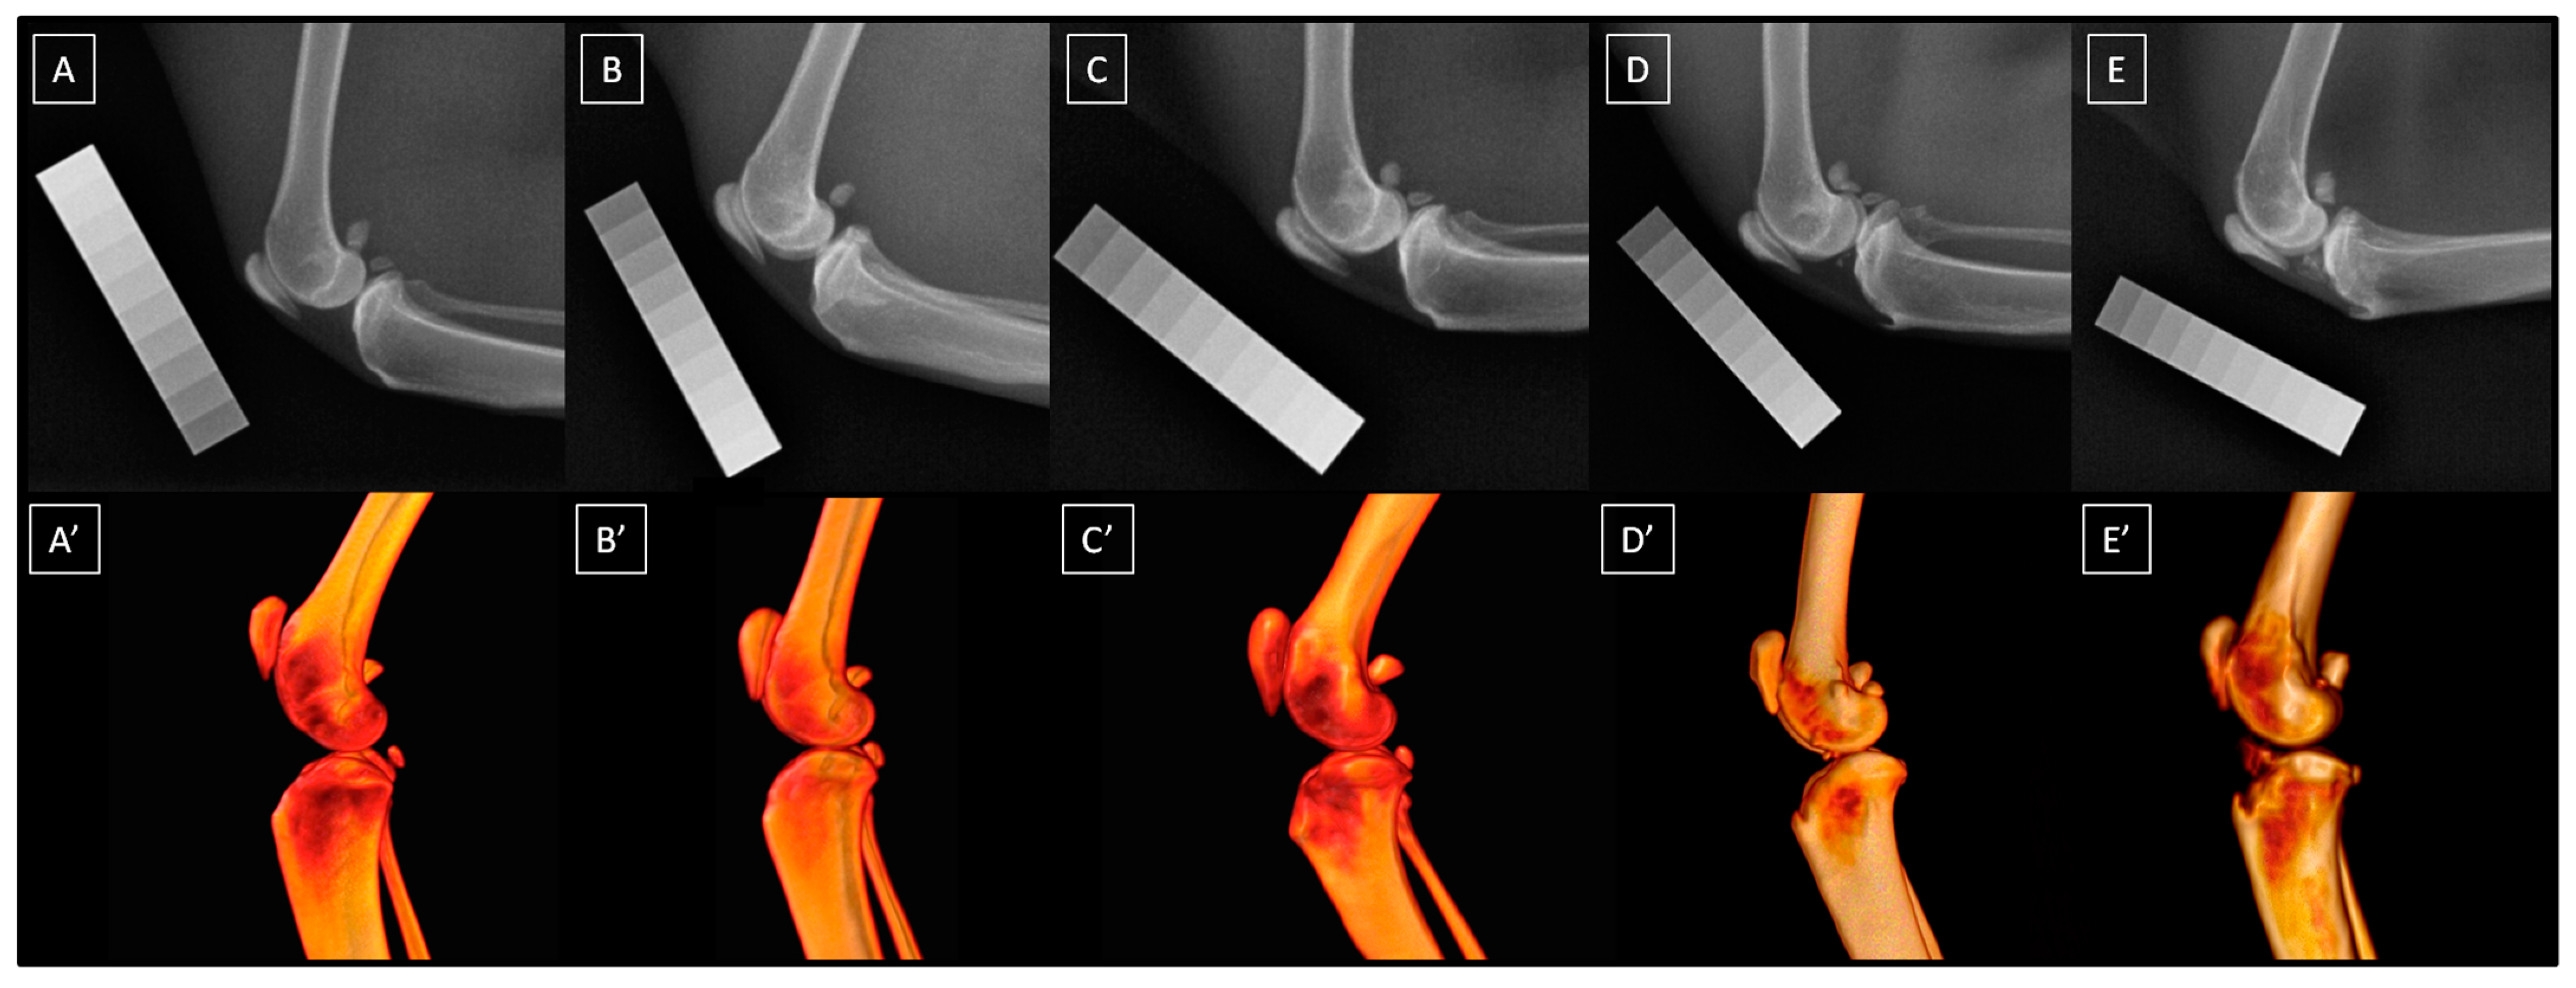

2.2.2. Image Collection Using Computed Digital Absorptiometry

2.4.2. Quantification of Computed Digital Absorptiometry Images

3.1. Descriptive Data